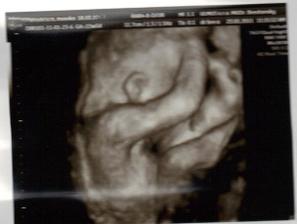

✿♥♥♥♥Bude to dievčatko!!!!! ♥♥♥♥✿

Bude to Stella 🙂

krasne 3D sono 🙂

Krasne foto dufam ze ti uz je lepsie mojko 🙂